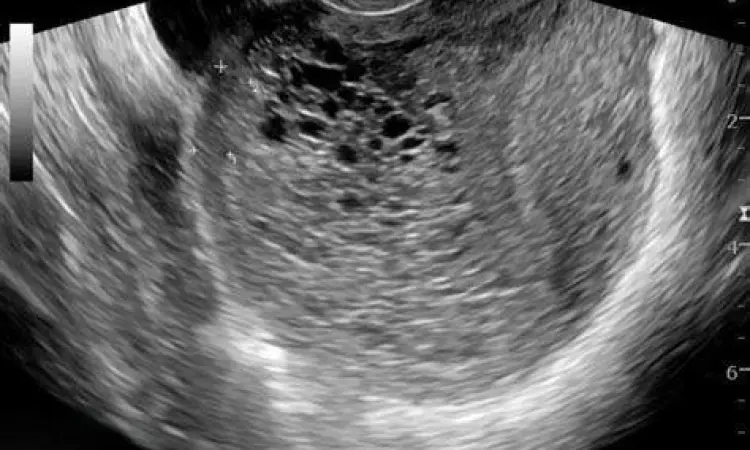

"Deteksi dini melalui pemeriksaan ultrasonografi (USG) adalah kunci utama. Gambaran 'snowstorm' atau badai salju pada layar USG merupakan tanda khas yang menunjukkan adanya jaringan kista di dalam rahim." - Pakar Ginekologi